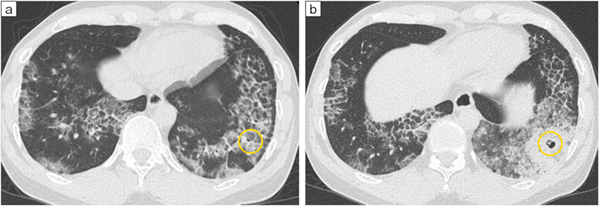

図16 Cアームを活用したクライオ生検2

a:生検前 b:生検後

図15の症例のCT画像。当院でのクライオ生検の結果、肺胞蛋白症と診断された。

Ultimax-iのCアームは、クライオ生検時に有用である。クライオ生検では、胸膜から1cm手前の位置が最も良質かつ安全に検体を採取できるとされており1)、そこでいかに確実に採取を行うかが重要なポイントとなる。生検中に介助者らが被検者の体位を変換し、保持している間に体が動いてしまうケースがあるが、Cアームを用いることで、被検者の体位を固定したまま最適な角度で検体採取が行える。前医が気管支肺胞洗浄(BAL)や経気管支肺生検(TBLB)を行ったが診断がつかず、当院でCアームを用いてクライオ生検を行った結果、肺胞蛋白症と診断された症例なども経験している(図15、16)。Cアームを有効に活用することで、病変やデバイスと胸膜との位置関係をより正確に把握し、安全に検査を行えることは、大きなメリットとなる。